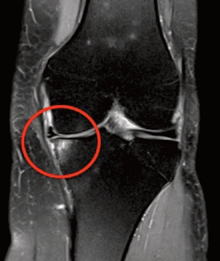

Varus (bow legs): MRI image below on the right shows how the medial (inner) compartment is failing; the articular cartilage is becoming thin and therefore greater load is having to be taken by the subchondral bone which shows up white, causing pain.